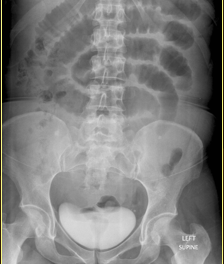

What type of bowel gas pattern?

Small Bowel Obstruction

What type of bowel gas pattern?

Large Bowel Obstruction

What type of bowel gas pattern?

Normal